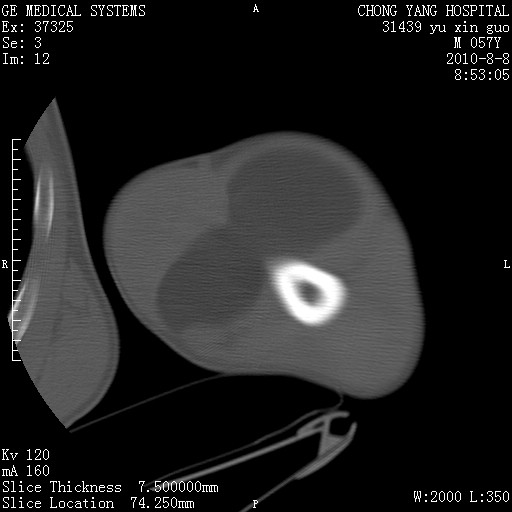

标题: CT28267:M57Y 上臂包块8年余。 [打印本页]

标题: CT28267:M57Y 上臂包块8年余。

软组织内脂肪瘤

包膜光滑、完整的脂肪密度肿块,支持脂肪瘤。